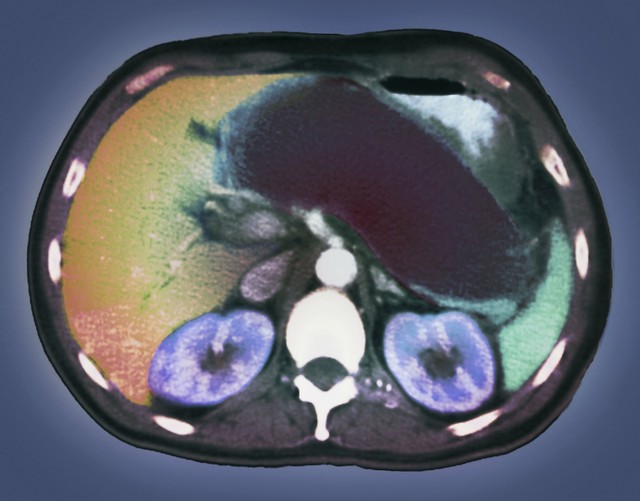

“医生,我乙肝多年,最近总没力气,是不是肝不好了?” 门诊里,很多乙肝患者因忽视身体异常,确诊肝癌时已到中晚期。乙肝病毒持续损伤肝脏,若不及时监测,可能悄悄发展为肝癌。其实从乙肝向肝癌进展时,身体会发出 4 个关键信号,别错过!

乙肝患者别等症状再检查!乙肝转肝癌早期症状不明显,上述信号出现时可能已不是早期。建议乙肝患者每 6 个月查一次肝脏超声 + 甲胎蛋白,尤其是 40 岁以上、有肝癌家族史的患者。早发现、早治疗,肝癌早期治愈率可达 70% 以上,别让 “拖延” 耽误病情。